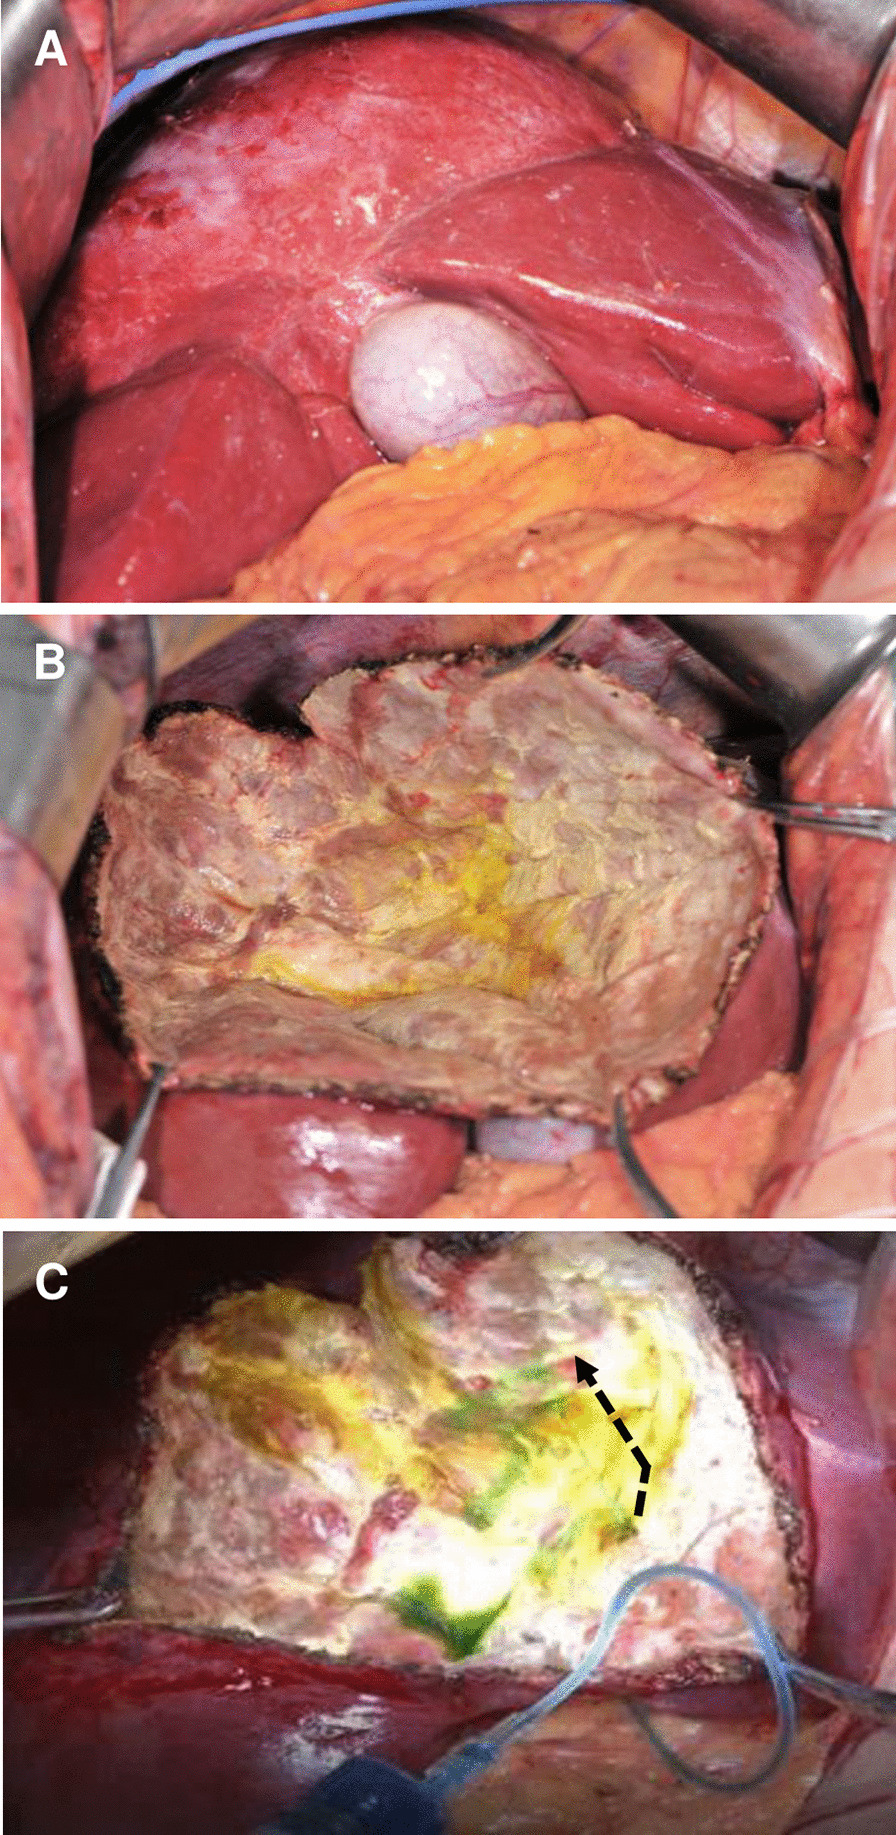

From 2007 March to 2012 December, altogether 660 hepatic CE patients have been hospitalized in our center, and 51 of which (3.5%) without hepatobiliary surgical history underwent PPC in our center due to CE with FCBC. Their most common complaints were abdominal pain, jaundice, nausea and fever. Patient demographics, cyst features and clinical symptoms were presented in Table 1. Preoperative computed tomography (CT) and magnetic resonance imaging and cholangiopancreatography (MR/MRCP) results indicated that, the certain bile duct where the rupture occurred, mostly were perihilar lobular bile ducts (Figs. 1 and 2). PPC was performed in all patients; debris in biliary tracts was removed through CBD using choledochoscopy after cholecystectomy; biliary tract was explored by injecting methylene blue (1:250 dilution with normal saline) to discover the FCBC site (Fig. 3). Owing to the basis of FCBC, setting decompression T-tube and sustaining T-tube drainage have been introduced. Consequently, we retrospectively divided these special subjects into two groups based on their operative procedures (double T-tube drainage group and single T-tube drainage group, specifically mentioned blow), forming this research cohort.

Schematic diagram (Fig. 4a) presented this procedure that was performed in 23 patients. In this method, main operation steps included: (i) PPC followed by exploration of inside surface of remnant peri-cyst to discover potential ruptured bile ducts; (ii) cholecystectomy, choledotomy and choledochoscopic exploration, removal of feces or debris in biliary tracts, biliary tree testing by infusing methylene blue through CBD, minor leakages in the residual cavity were sutured by using 4-0 or 5-0 absorbable sutures; (iii) upon exposuring FCBC site, one sustaining T-tube was placed where it ruptured, followed by a regular decompression T-tube at the CBD was introduced, thereafter, the rupture and the biliary tracs were reexamined by flushing methylene blue through decompression T-tube until no leakage was noticed; (iv) after careful examination and assuring patency of biliary tree, other two routine catheters were placed respectively at the residual cavity and the hepatic hilar region for post-surgical observation of any bile leakage or infections.

Schematic diagram (Fig. 4b) showed this procedure that was performed in 28 patients. Main steps (i), (ii) and (iv) were same with above approach; (iii) the specific ruptured bile duct was sutured using 5-0 or 6-0 absorbable sutures, then a regular decompression T-tube at CBD was introduced, thereafter, reexamination by flushing methylene blue through T-tube was performed until no leakage was noticed.